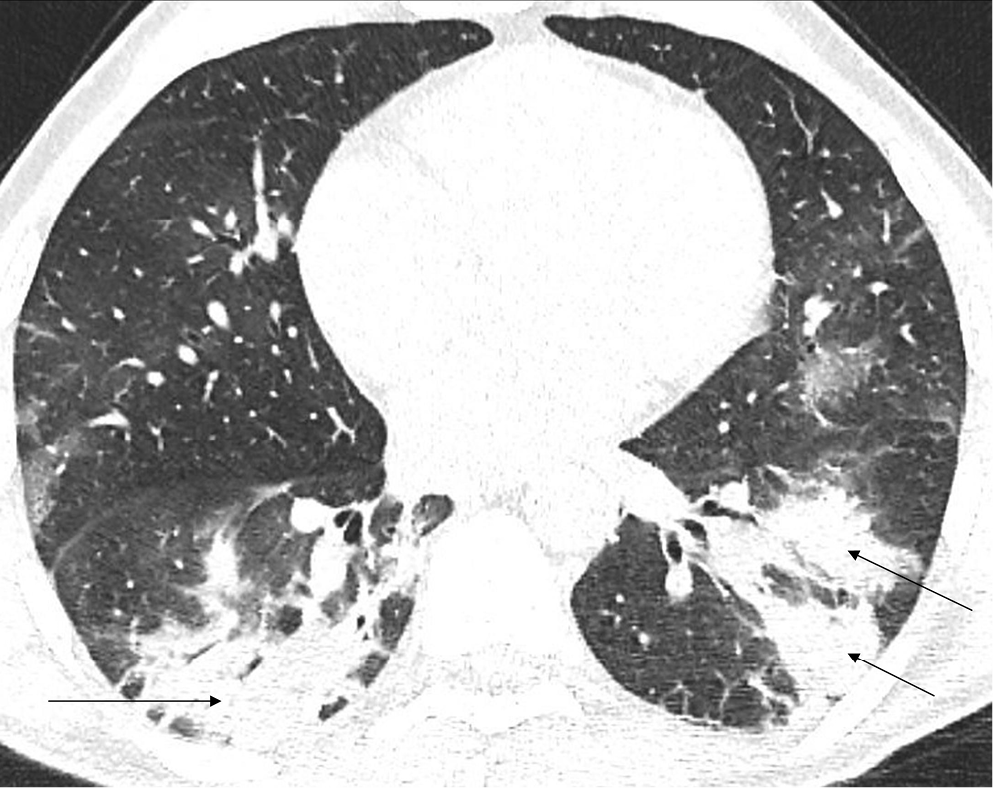

In the early stage of COVID-19, the primary CT findings observed are bilateral GGOs with a mostly peripheral and subpleural location. Ground-glass opacity is a term used to describe hazy areas with the preservation of vascular and bronchial margins which are a result of the partial filling of air spaces, intestinal thickening, or the coexistence of both (Figure 2).10 Another phenomenon is described as having ‘crazy-paving’ appearance. This is a combination of GGO and interlobular or intralobular septal thickening (Figure 3). This condition is mostly present in severe cases of COVID-19 pneumonia. Consolidations (multifocal, patchy or segmental) are another sign of COVID-19 progression (Figure 4).11 Several days after developing the first symptoms, chest CT can reveal linear consolidations and reversed halo signs in the patient’s lungs.12 Radiographic features typically include bronchovascular thickening (Figure 5).13

A retrospective study of 121 symptomatic patients infected with SARS-CoV-2 was performed by Bernheim et al.15 The main aim of their research was to assess the correlation between the onset of symptoms and common findings on the initial CT scan. The time between the occurrence of the first symptoms and subsequent CT scans was divided into 3 periods: early (0–2 days); intermediate (3–5 days); and late (6–12 days). Bilateral lung evolvement, which is considered typical in COVID-19 pneumonia, was observed in 28% of early-stage patients, 76% of intermediate-stage ones and 88% of late-stage patients. Crazy-paving appearance and the reversed halo effect were absent in the early group, but were mostly present in the late-stage group. It was found that 56% of the early patients showed the lack of lung capacities during the radiological examination despite the presence of clinical symptoms. The study results exhibit imaging patterns, essential not only for understanding the pathophysiology or natural history of COVID-19, but also for the prediction of its progression and potential complications.15

Based on similar research, 4 stages of CT imaging have been established. The 1st stage is named the early or initial stage and lasts up to 4 days. A CT scan performed during this period may not reveal any pathologies or may only indicate the presence of GGOs. It is crucial to remember that up to half of patients may have a normal CT scan 2 days after the symptoms occur. The next phase is the progressive stage (5–8 days) – several GGOs arise and the crazy-paving pattern becomes visible. Between 9 and 13 days, consolidations appear. This phase is called the peak stage. After 14 days, absorption begins and fibrous stripes may occur (Figure 6). After at least 1 month, and if no other complications arise, the patient’s lungs are able to return to a condition similar to that before COVID-19.16